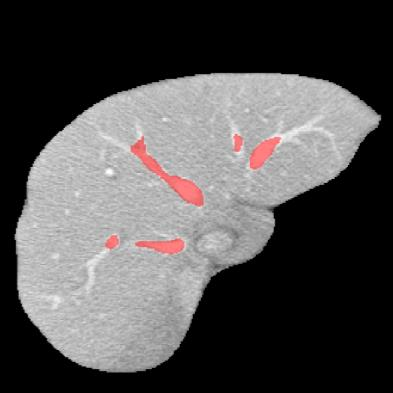

Manually segmenting the hepatic vessels from Computer Tomography (CT) is far more expertise-demanding and laborious than other structures due to the low-contrast and complex morphology of vessels, resulting in the extreme lack of high-quality labeled data. Without sufficient high-quality annotations, the usual data-driven learning-based approaches struggle with deficient training. On the other hand, directly introducing additional data with low-quality annotations may confuse the network, leading to undesirable performance degradation. To address this issue, we propose a novel mean-teacher-assisted confident learning framework to robustly exploit the noisy labeled data for the challenging hepatic vessel segmentation task. Specifically, with the adapted confident learning assisted by a third party, i.e., the weight-averaged teacher model, the noisy labels in the additional low-quality dataset can be transformed from "encumbrance" to "treasure" via progressive pixel-wise soft-correction, thus providing productive guidance. Extensive experiments using two public datasets demonstrate the superiority of the proposed framework as well as the effectiveness of each component.